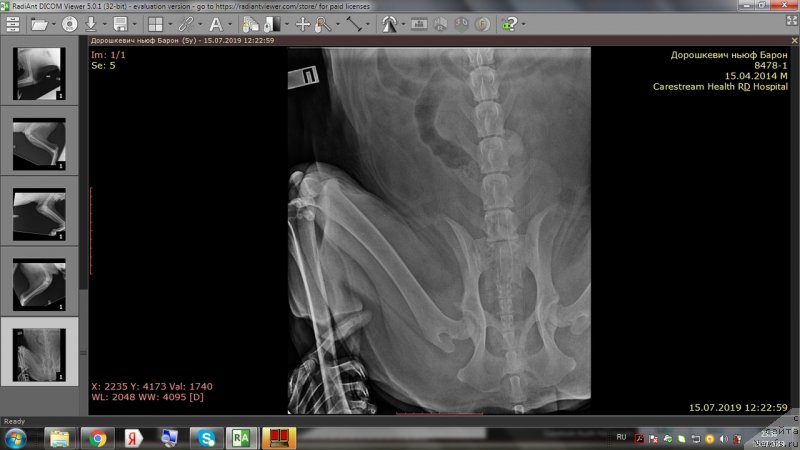

На приёме у врача.

Фотография № 243974

Фотография № 243976

Фотография № 243977

Фотография № 243978

Доброе утро,уважаемые форумчане!Вот и проползли черепашкой эти томительные 2 недели до повторного приема врача.И,вновь,к нашей радости,не подтвердились самые худшие опасения😊.Барошенька похудел на 3 кг.На снимках,как видно,в более-менее живом состоянии только правое колено.Локти не сгибаются из-за махровых наростов,с левым коленом ситуация хуже остальных лап,на прогулке,после лежания,первые несколько метров в колене слышно перестукивание суставов,но потом все проходит.Лечение идёт на пользу,колени стали лучше сгибаться,огромный отёк с левого колена спал,и писает теперь не приседая полностью до земли и не плюхаясь пузом от усталости в свою лужу.На прошлой неделе созванивались с доктором и немного подредактировали терапию-отменили тобрекс,т.к.не было результата и заменили на офтагель,флоксал,в связи с тем ,что у Бароши синдром сухого глаза и заворот века(рекомендовано в будущем провести операцию).Сегодня обновлю запасы этих лекарств.Антибиотик доксифин продлили до 8 недель,но купила пока на 2 недели,т.к.финансов не хватит на такой курс.Полное,качественное восстановление займет месяца 2.Сейчас то тут,то там выскочит экзема,соскоб с экзем показал наличие грибов-коки,эзофилы.Тут и стресс перенесенный и смена климата и т.д.